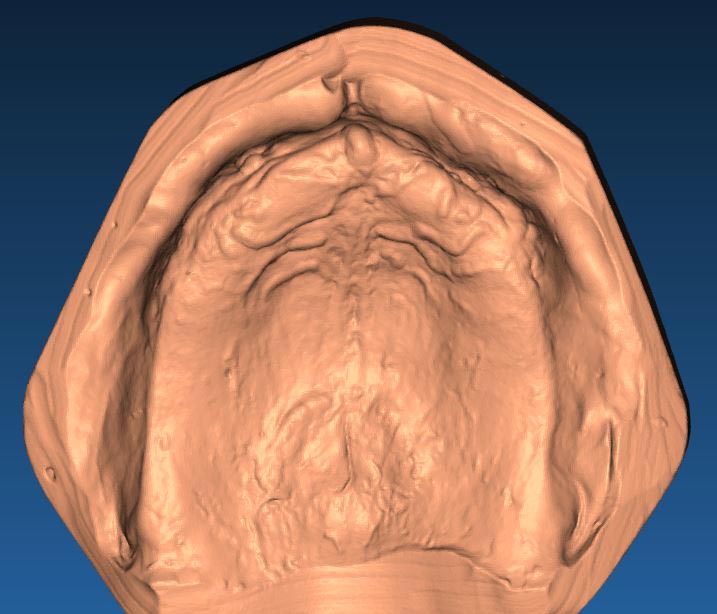

anatomia

Matching DCM Stl

Matching effettuato

Segmentazione del mascellare, senza i denti

Segmentazione eseguita